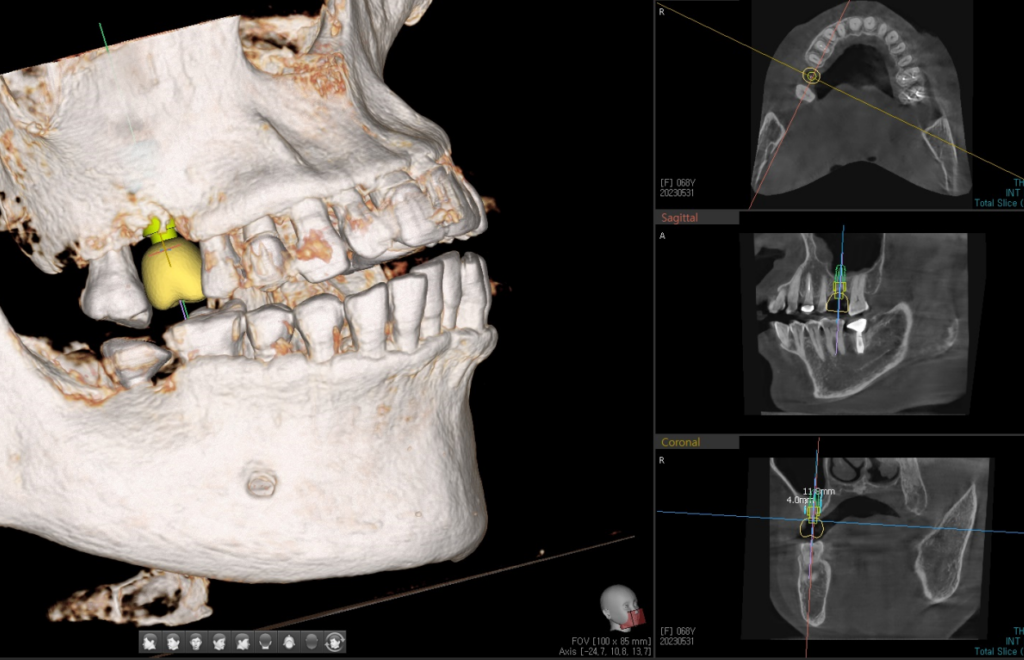

23. 02. 24(CT를 활용한 모의 임플란트 수술)

CT를 활용한 모의 임플란트 수술 여러분들은 그림을 그릴때, 어떤 방식으로 그림을 그리시나요?

처음에는 밑그림을 그리고, 나중에 그 밑그림이 내 생각과 정확하게 맞다면 그다음에 디테일을 생각하시지 않나요?

임플란트 치료도 그렇습니다. 먼저 임플란트라는 것을 왜 해야하는지에 대해서 생각하면서 환자분에게 맞춤형으로 치아의 머리 부분이 들어가는 것을 디자인하고 그 치아 머리부분에 씹는 힘이 가장효율적으로 전달될 수 있도록

임플란트 뿌리 부분을 설계하고 식립합니다.

임플란트 치료 : Top – down process

이는 임플란트 치료에 있어 Top-down 방식으로 명명하며, 교합적으로 안정적인 위치에 보철물이 만들어질 수 있도록, 치아 머리를 먼저 설계 후 뿌리부분의 길이와 위치를 설정하는 것이 임플란트의 장기적인 예후에 좋다는 것이 이 방식의 컨셉입니다.